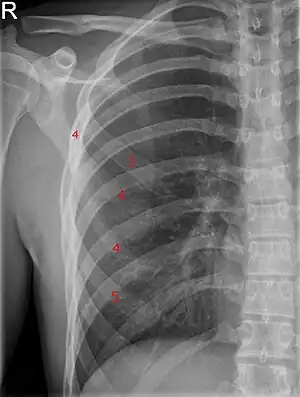

Bifid rib at the right side seen on chest radiograph. The fourth rib splits in two towards the sternal end.

A bifid rib is a congenital abnormality of the rib cage and associated muscles and nerves which occurs in about 1.2% of humans. Bifid ribs occur in up to 8.4% of Samoans.[1] The sternal end of the rib is cleaved into two. It is usually unilateral.

a,b) Upper intercostal space of the bifid fourth rib was narrow